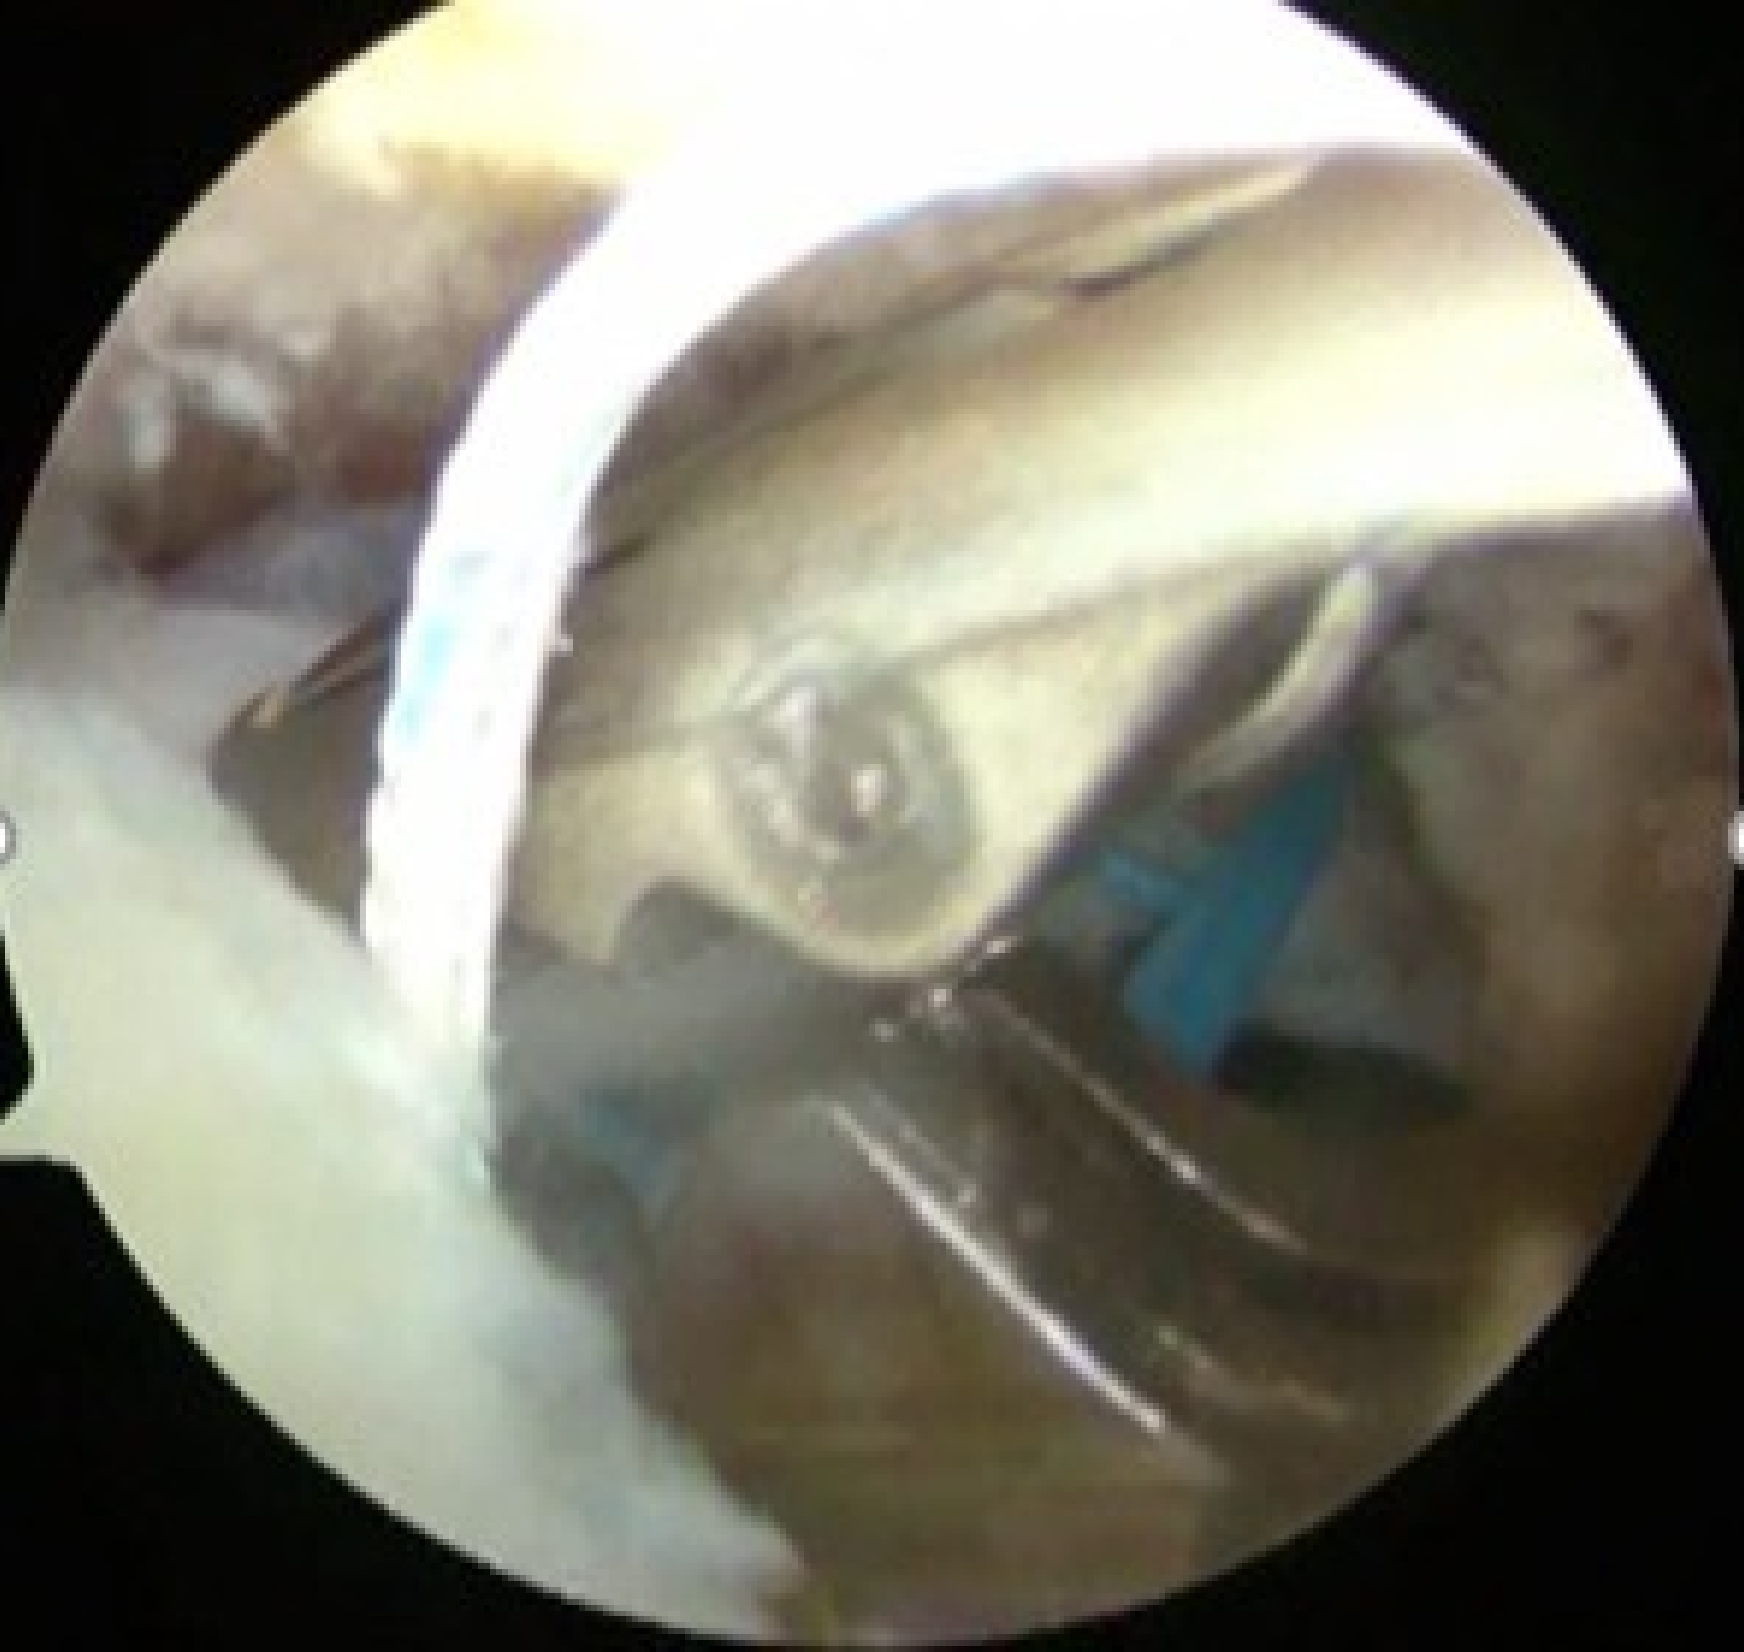

U字型の中断裂

上腕骨頭(大結節Footprint)が露出してしまっている。